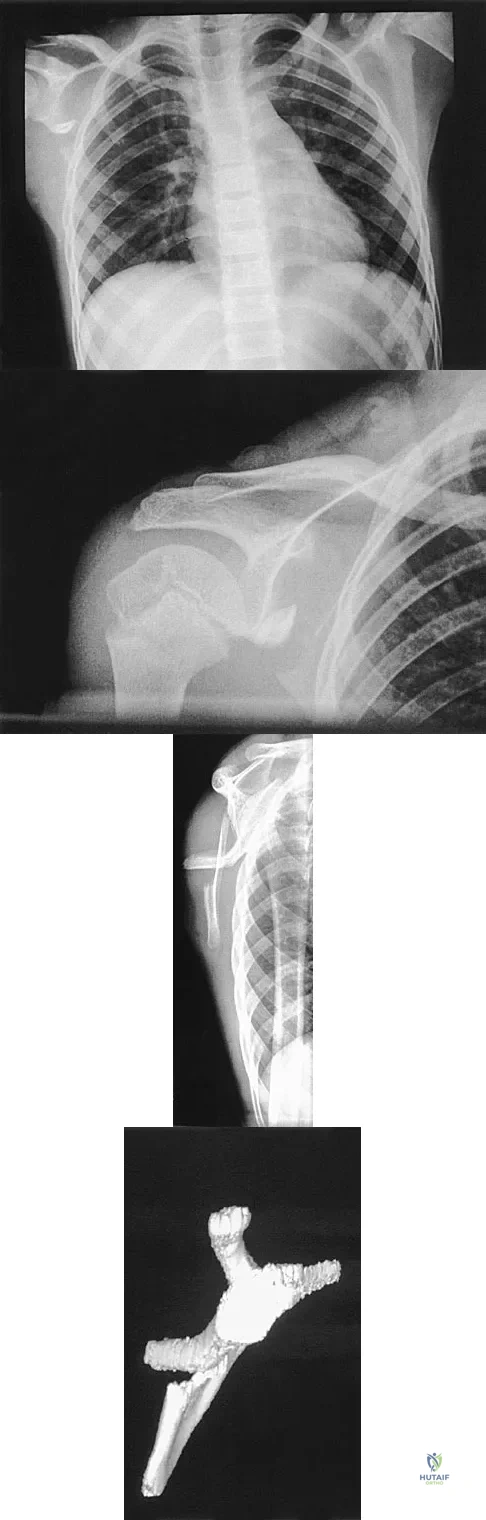

A 12-year-old boy has severe left shoulder pain after being struck by an automobile. A chest radiograph, AP and lateral radiographs, and a CT scan with three-dimensional reconstruction of the scapula are shown in Figures 38a through 38d. Management should consist of